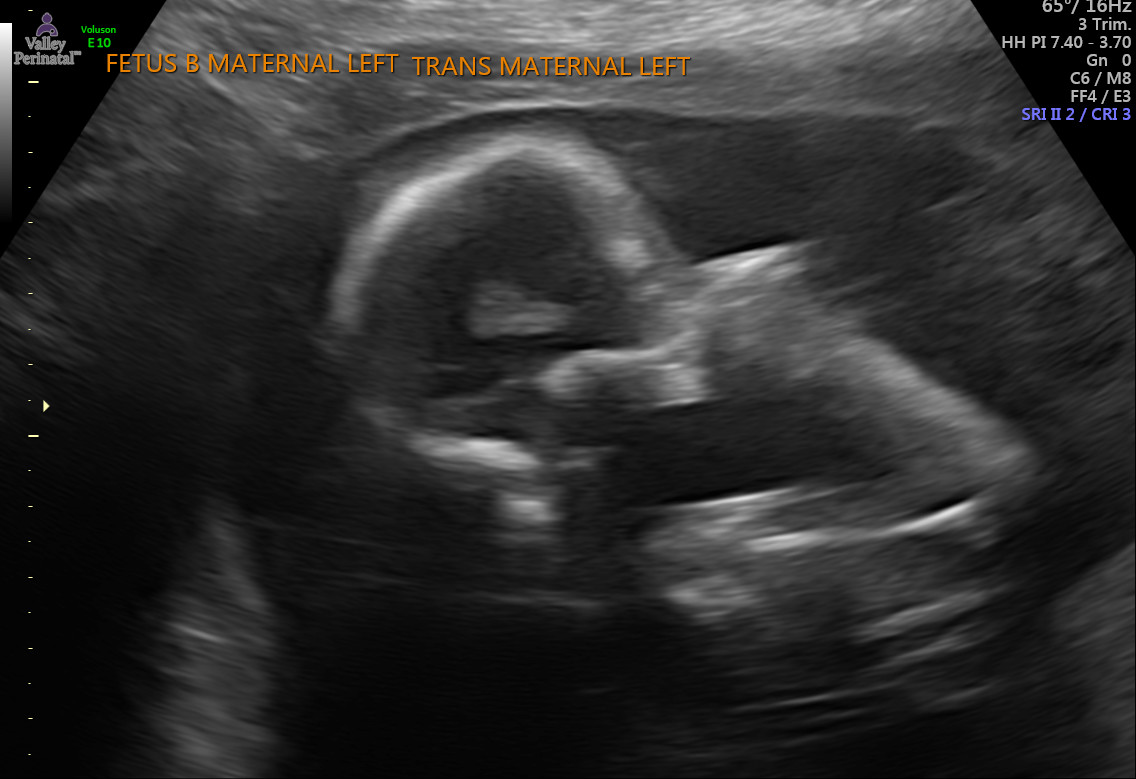

Look how cute you guys are!!! Apparently the tech forgot to send me some pictures of you Baby B :( Unfortunate. But there will be more to come with the amount of appointments I have haha.

Today I was able to have another ultrasound at the OB's office. It was just a quick check up on your heartbeats. Here are the pictures they got.

Here are some pictures we got printed out at the appointment.